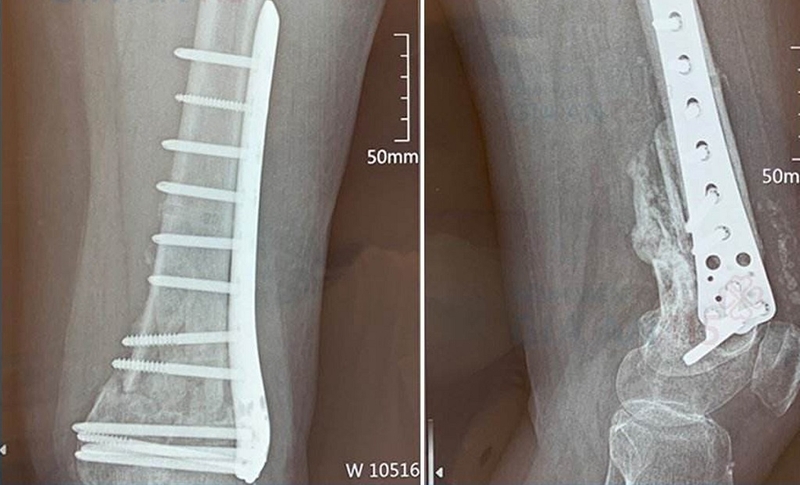

• Ghép xương: Mảnh xương thay thế được cố định vào vị trí cần ghép bằng các thiết bị như đinh ghim, đĩa, ốc vít, dây, cáp hoặc các kỹ thuật khác. Mục tiêu là đảm bảo rằng xương ghép vừa vặn hoàn hảo và ổn định trong quá trình phục hồi.

Ghép xương: Phương pháp khôi phục và tái tạo xương sau chấn thương 2

Mảnh xương thay thế được chuẩn bị với kích thước và hình dạng phù hợp với vùng cần ghép